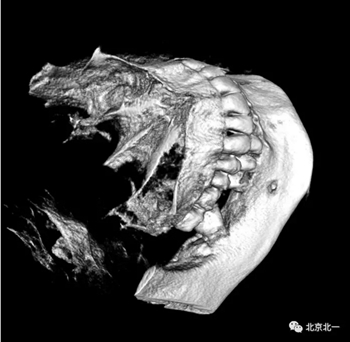

檢查:46缺失, 47傾斜, 1度松動, 未見48萌出,

CBCT:骨量高度及寬度可, 48埋伏,低位阻生.37近中骨吸收

診斷:下頜牙列缺損, 48低位埋伏阻生 37 牙周炎

治療計劃:46種植, 同期拔除48 正畸扶正47.